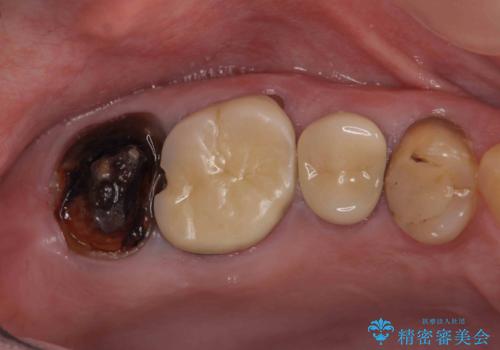

- 近医で「根尖の病変が大きく、残すことができない、歯を抜くしかない。」、と言われ歯を抜く以外の手段がないかを相談しに来院されました。

検査の結果、根管・クリアランス・虫歯といった複合的な問題が認められ、以下のような治療計画を進めることとしました。

根尖病変 →マイクロスコープを用いた精密根管治療の実施